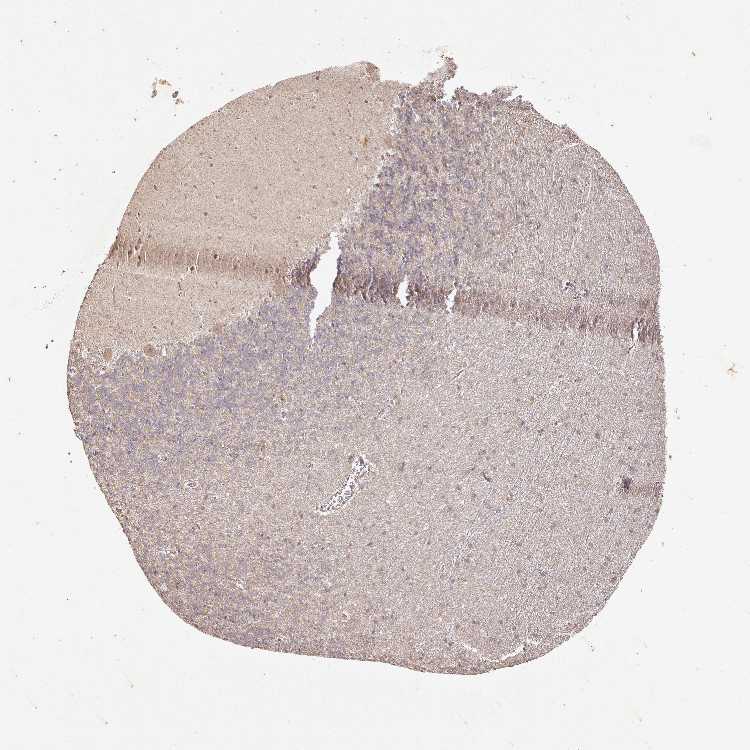

CEREBELLUM - Antibody stainingi

Antibody staining in the annotated cell types in the current human tissue is reported as not detected, low, medium, or high, based on conventional immunohistochemistry profiling in selected tissues. This score is based on the combination of the staining intensity and fraction of stained cells.

Each image is clickable and will lead to virtual microscopy that enables deeper exploration of all samples and also displays staining intensity scores, fraction scores and subcellular localization as well as patient and tissue information for each sample.

Antibody CAB033237

Purkinje cells Medium

Cells in granular layer Low

Cells in molecular layer Not detected